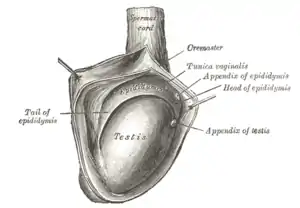

| The right testis, exposed by laying open the tunica vaginalis. (Tunica vaginalis is labeled at upper right.) | |